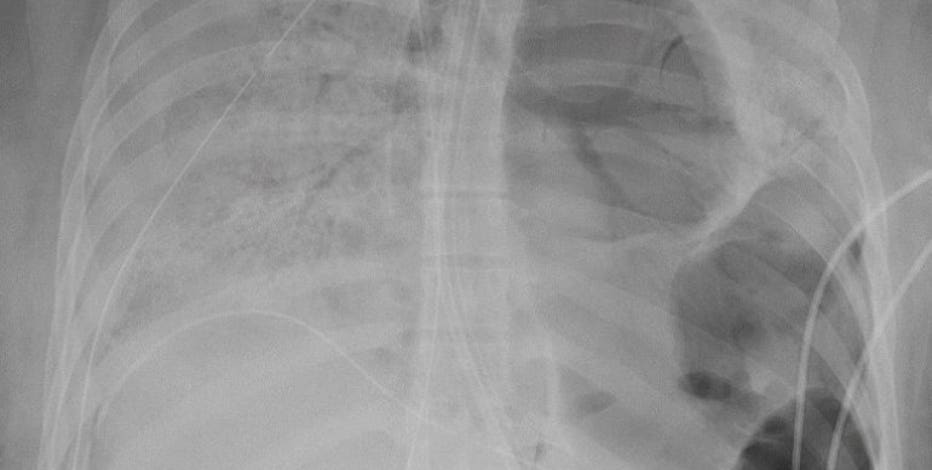

The study examines the chest x rays and ct scans from over 20 patients aged 10 74 years with symptoms of covid 19. This is how covid 19 can damage your lungs why you can trust sky news x ray images and ct scans of coronavirus patients reveal how their lungs are being ravaged by the virus and filled with a sticky mucus that prevents them from inhaling because there is no space for air. X rays and ct scans of coronavirus victims have emerged showing the shocking damage covid 19 does to peoples lungs.

On a chest ct they may see something. These x ray images show the damage that coronavirus is doing to the lungs of people who catch the potentially deadly bug. On chest x ray the most suggestive imaging pattern for covid 19 in children is bilateral peripheral predominant ggo or consolidation in the mid and lower lung zones says foust.

While patients with covid 19 can show an abnormality on either a chest x ray or ct scan many other lung problems can look very similar. Some people have pneumonia a lung infection in which the alveoli are inflamed. X ray images of coronavirus infected lungs show how the virus damages the respiratory system chest radiography of confirmed coronavirus disease 2019 covid 19 pneumonia a 53 year old female.

Doctors have been able to identify specific abnormalities caused by. The scans showed inflamed lungs with ground glass opacities which look like. While covid 19 test kits have been in limited supply new studies from china suggest chest radiographs x rays and chest computed tomography ct scans can help diagnose the disease.

This was usually done with a ct scan or chest x ray.